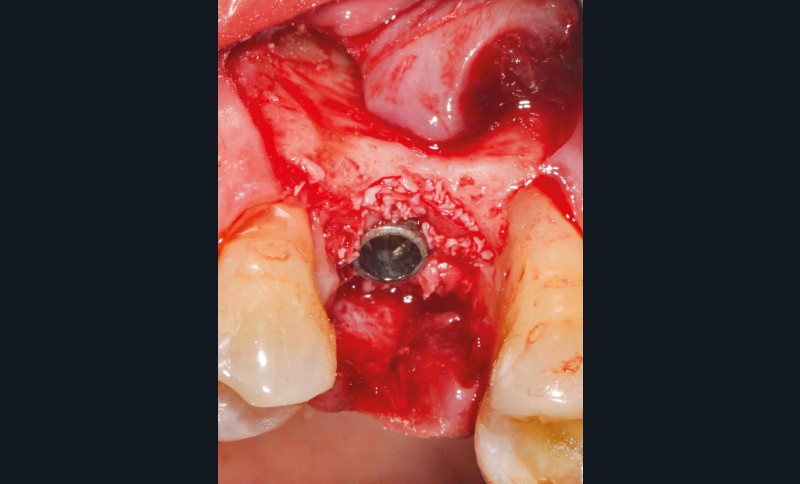

L’implant

- Posé en 2019 par son dentiste

- Couronne d’usage transvissée

- Péri-implantite diagnostiquée en 2020

Chez cette patiente, le traitement de la péri-implantite a été réalisé à l’aide d’une technique de régénération osseuse guidée péri-implantaire, dont l’indication a été principalement motivée par la morphologie du défaut osseux. Au-delà de la maîtrise du geste chirurgical, le bon résultat obtenu à trois ans est intimement lié à sa coopération en termes de suivi et de contrôle de plaque.